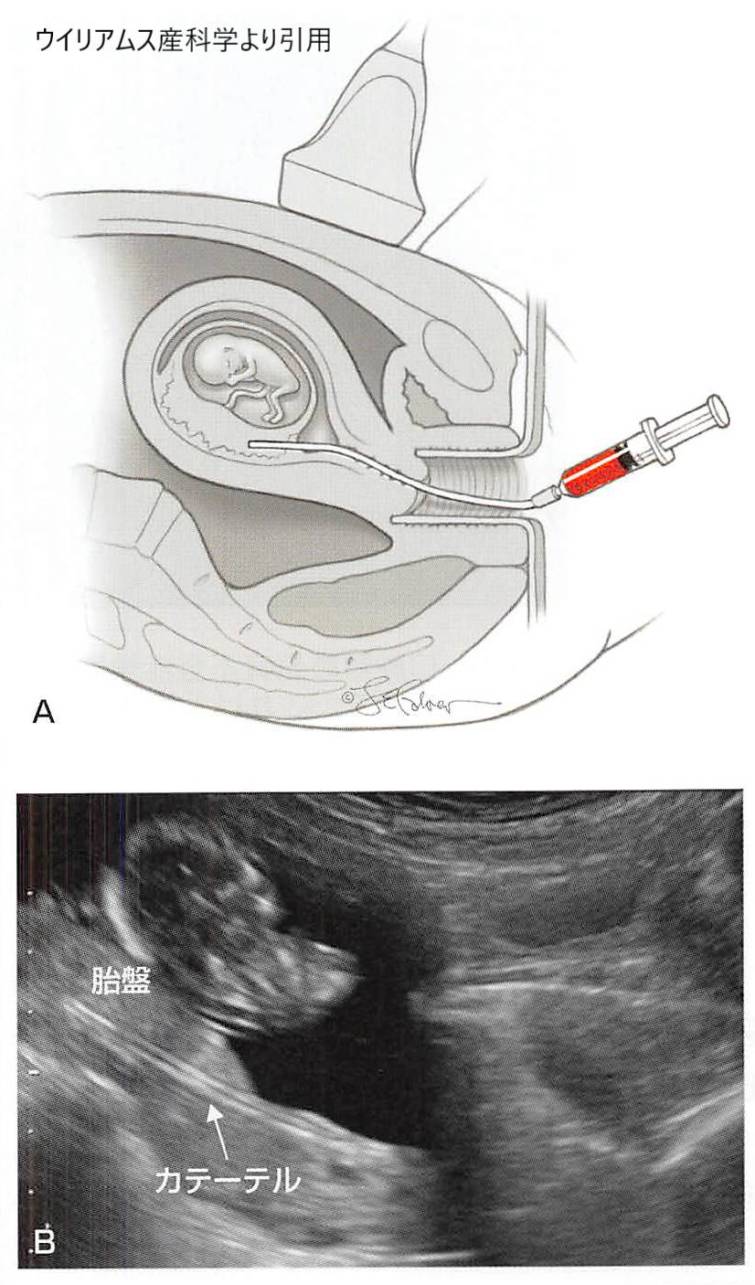

絨毛検査(CVS)は、検査のために胎盤から絨毛のサンプルを採取する出生前検査です。サンプルは、子宮頸管(経膣)または腹壁(経腹)から採取することができます。

絨毛の採取は通常、妊娠第11週から第14週の間に行われ、羊水穿刺などの他の出生前診断検査よりも早く行われます。